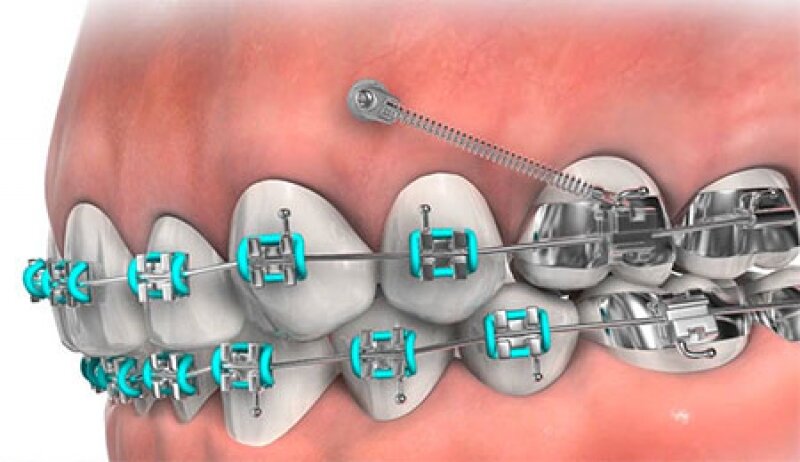

that would work but would probably recess the fuck out of me but it is always an optionView attachment 4175991

found this, no fucking clue what it is but looks like it does the job and recesses your maxilla pretty sure

Not going to be bimax-tier unless jaw discrepancy is spotted which your ortho probably ruled out. In all honesty, they might go the safe route of premolar extractions which isn’t what you want. Perhaps TAD-anchored mechanics of sorts (?), they do these in aligners/braces I’m aware of, but not sure of what else, or if they’re even suitable for you / if your ortho is qualified to use them.

View attachment 4176123View attachment 4176124